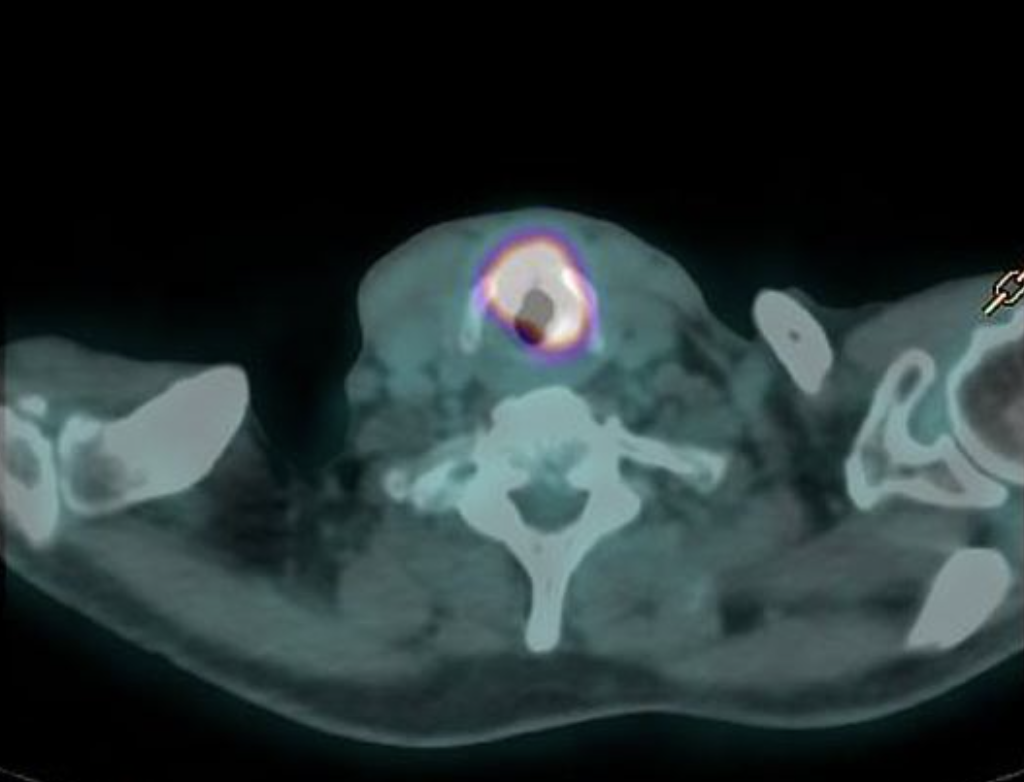

Positron emission tomography (PET) typically involves injecting a radioactive sugar solution (FDG) into your veins, which is absorbed by cancer cells because they are actively using sugar metabolism to grow. Other normal organs such as the brain will light up because those cells also preferentially use sugar for its energy source. After some time to allow the sugar to be taken up, you will be scanned in a combined PET and CT scanner. The low level radiation from FDG will be detected by the scanner and overlaid on the CT scan. This scan is useful because it is more sensitive than a CT scan for detecting cancer metastasis/spread.